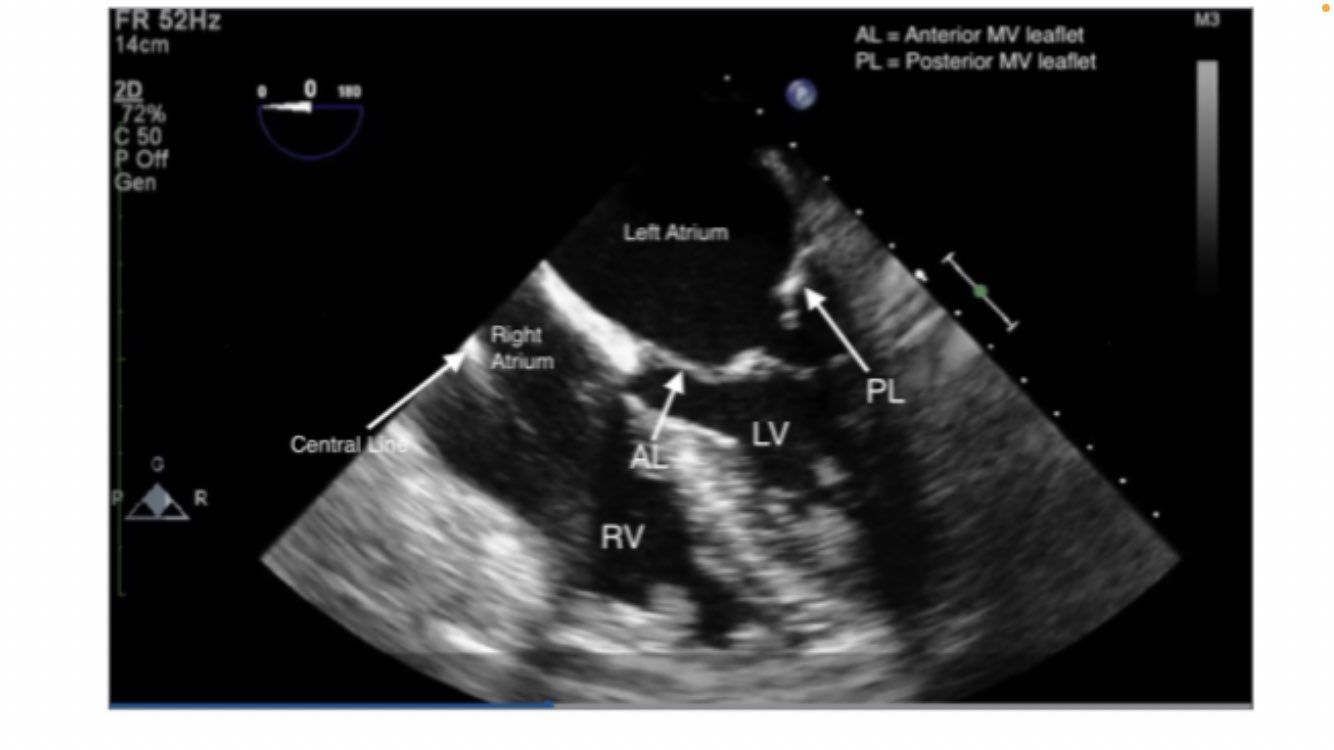

midesophageal 4 chamber

Midesophageal 4 chamber view